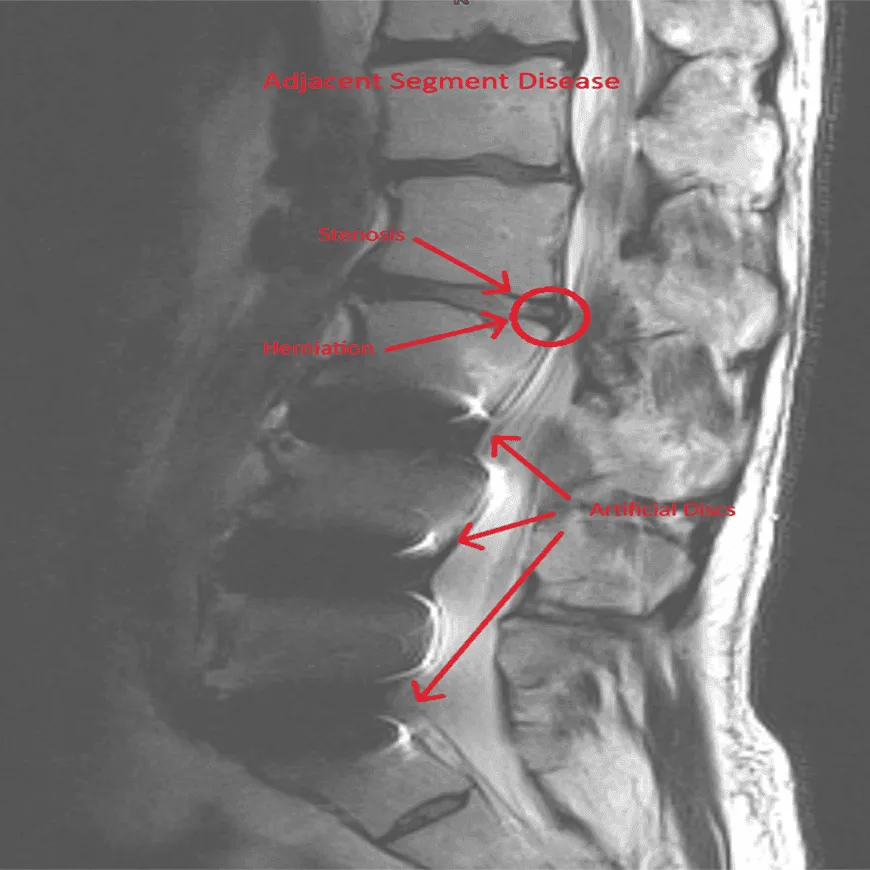

Adjacent Segment Disease

MRI of the spine showing herniation and fusion marked with arrows.

Recurrent Disc Herniation

Fusion forces adjacent segments to compensate, accelerating degeneration and instability.